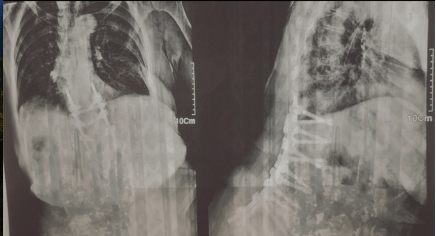

La interpelación directa que hace a cámara su madre, donde le pide el libro del Corán y que ella (Firouzeh) desde la operación de la cámara, se lo entregue y después use esa misma mano para poner otro velo a la imagen, la radiografía, genera que estas acciones se conjuguen como la forma de convivencia actual entre hija y madre en un cierre que establece un relato meta fílmico dentro del universo narrativo que plantea la película y da título a ella (Figura 19, 20, 21, 22 y 23).

Figura 22. Fotogramas de la película. Plano secuencia de la película que culmina con la pantalla «velada» por la presencia de la radiografía.